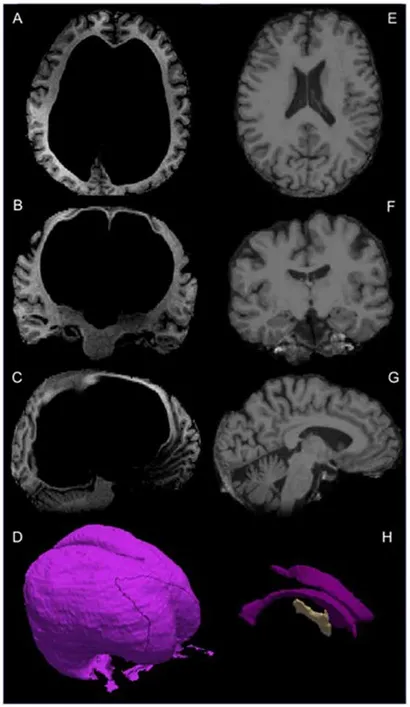

重度脑积水的儿童头颅:

LOVA 虽然往往也起源于幼儿,但由于发展缓慢以及治疗等原因,大脑得到成熟发育,虽然最终依旧在成年阶段发展为脑积水。

在漫长的发展过程中,虽然大脑皮层被压缩得越来越薄,但因为长期代偿,依旧可能维持正常功能。